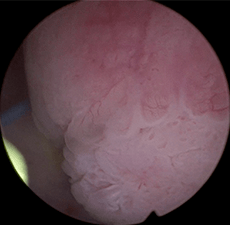

Ureteroscopy and biopsy confirmed a large papillary renal pelvis tumor consistent with LG-UTUC.

Patient underwent left percutaneous resection followed by 6 once-weekly antegrade instillations of Jelmyto for the treatment of residual disease.